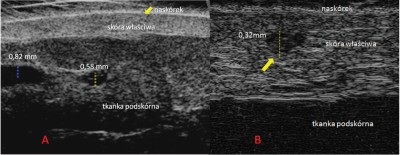

Innowacyjnym urządzeniem, które charakteryzuje wysoka użyteczność zarówno na etapie diagnozy, jak i później, w trakcie wykonywania zabiegu, jest ultrasonograf wysokich częstotliwości [6]. Dzięki zastosowaniu głowic o częstotliwości wyższej niż 20 MHz uzyskujemy obraz ultrasonograficzny o wysokiej rozdzielczości, na którym można różnicować obiekty mniejsze niż 0,1 mm. W trakcie badania za pomocą ultrasonografu wysokich częstotliwości można dokładnie ocenić przebieg i położenie drobnych naczyń w skórze. Dzięki tej technologii możliwe stało się obrazowanie teleangiektazji, co przez wiele lat było zupełnie niedostępne (fot. 3).

Fot. 3 Ocena drobnych naczyń krwionośnych za pomocą ultrasonografu wysokich częstotliwości. A – naczynia położone w tkance podskórnej (aparat Derma View Dramiński z głowicą 48 MHz, B – teleangiektazje w skórze właściwej (aparat Episcan z głowicą 50 MHzW praktyce, autorzy przyjęli standard, że osoba zgłaszająca się z problemami naczyniowymi w pierwszej kolejności trafia do kosmetologa, gdzie przeprowadzany jest szczegółowy wywiad, ocenia się wstępnie naczynia, korzystając z przedstawionych w artykule metod, i omawia się z pacjentem możliwości ich likwidowania. Rolą kosmetologa jest zebranie jak największej ilości informacji od pacjenta, uporządkowanie ich i przekazanie lekarzowi. Również podczas pierwszej wizyty kosmetolog powinien wykonać dokumentację fotograficzną, która później posłuży do oceny efektu prowadzonych działań. Następnie pacjent kierowany jest do lekarza. I tutaj zazwyczaj mamy dwie możliwości: albo zostanie dobrany i wykonany zabieg, albo zanim zostanie zaplanowane leczenie, wykonuje się klasyczne badanie ultrasonograficzne USG Dopplera (Doppler ultrasonography).